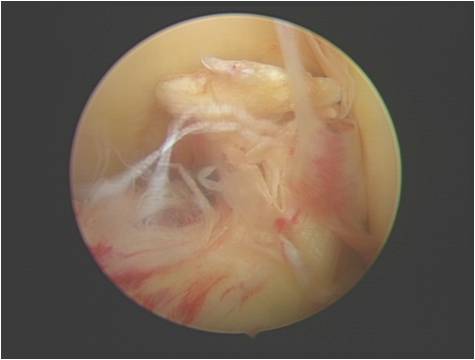

交叉韧带重建